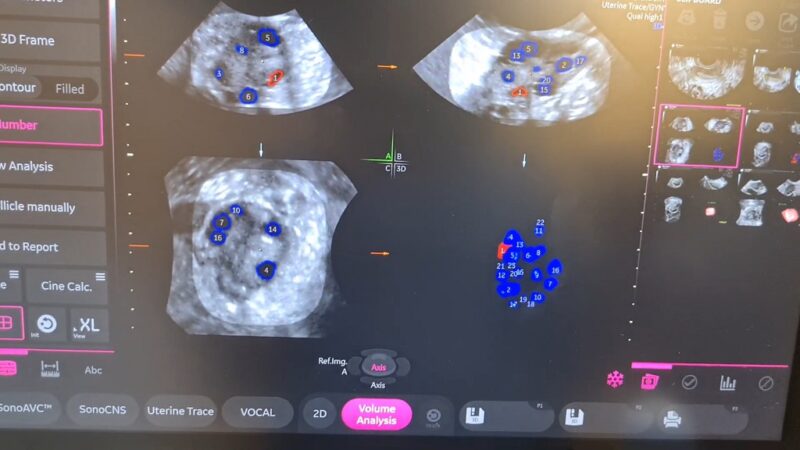

Antral Follicle Count (AFC) is a transvaginal ultrasound measurement that counts small ovarian follicles early in the menstrual cycle to estimate ovarian reserve. It helps predict response to fertility treatments such as IVF, guides reproductive planning, and identifies possible hormonal conditions affecting the ovaries.

Antral follicles are small fluid-filled structures in the ovaries that each contain an immature egg. They are visible through ultrasound when they reach approximately 2–10 millimeters in diameter. The number of these follicles correlates with the remaining pool of primordial follicles, which gradually declines with age. AFC therefore acts as a proxy for ovarian reserve rather than a direct measure of fertility.

Clinically, AFC is measured during the early follicular phase of the menstrual cycle, typically days 2 through 5, when hormonal activity is relatively stable. Measuring outside this window may produce misleading counts because dominant follicles or luteal activity can obscure smaller follicles.

The test is widely used because it is non-invasive, relatively inexpensive compared with laboratory fertility testing, and provides immediate visual confirmation of ovarian structure and follicle distribution.